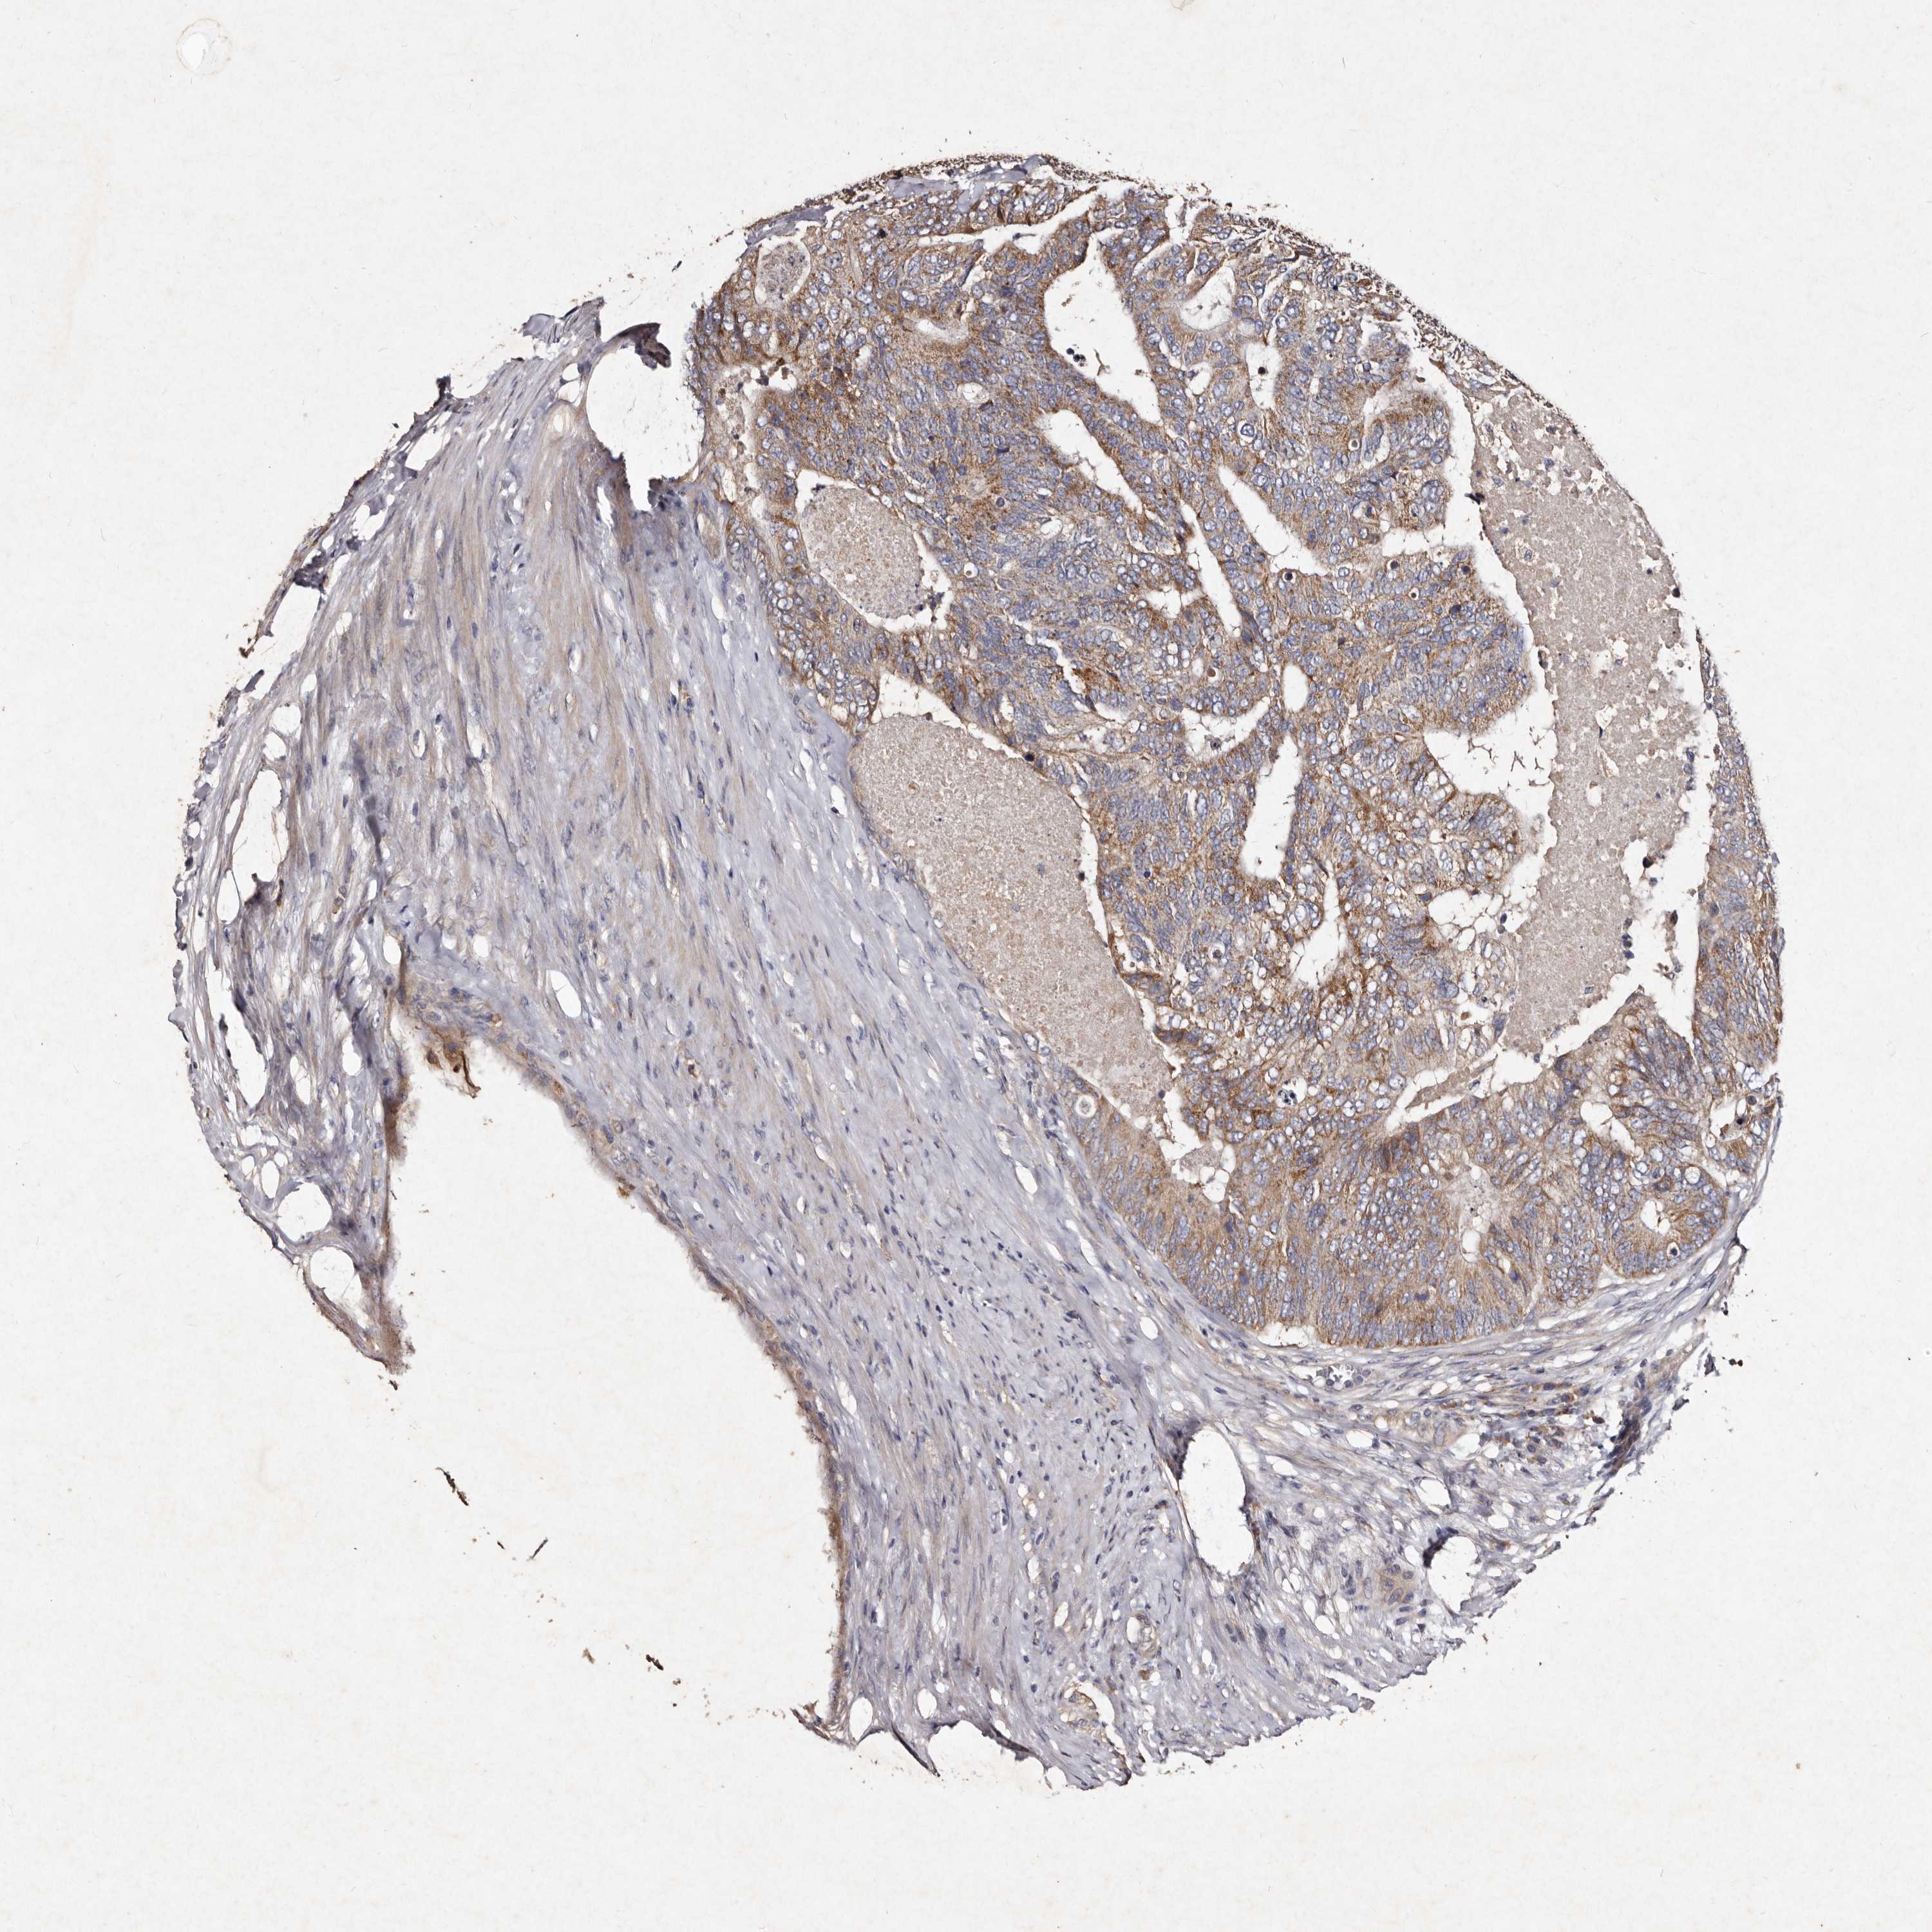

CANCER COLORECTAL CANCER Show tissue menu

Colorectal cancer

Human cancer

Colon adenocarcinoma